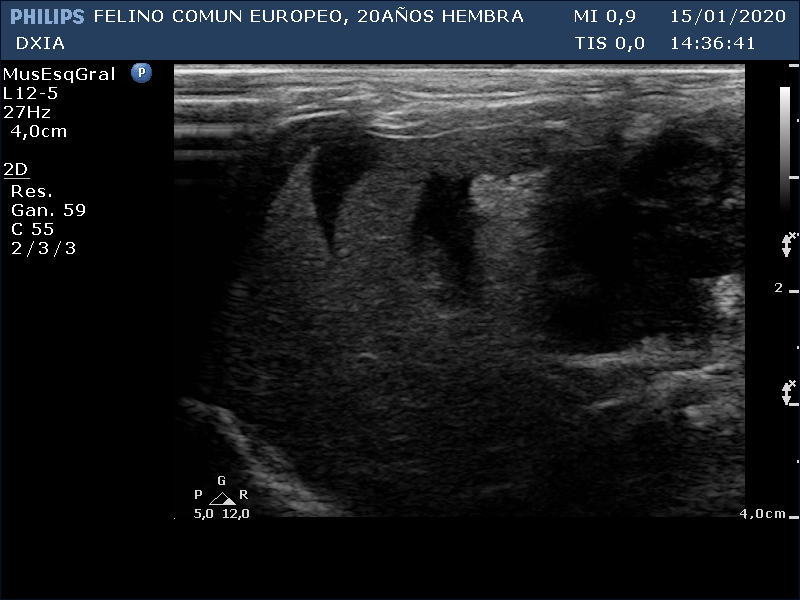

FRANGELICA

Se realiza ecografía y se observa alteración compatible con neoformación en asa del intestino delgado.

Parénquima hepático homogéneo. Vesícula biliar de pared fina e hiperecogénica. No presencia de barro biliar. Distensión del conducto biliar.

Asa del ID con aumento de grosor de su pared, pérdida de estructura en capas. Neoformación hipoecogénica.

Lóbulos hepáticos con bordes afilados y parénquima homogéneo. Se observa presencia de líquido libre anecogénico entre dichos lóbulos.

Asa del ID con neoformación sin definición de capas intestinales.